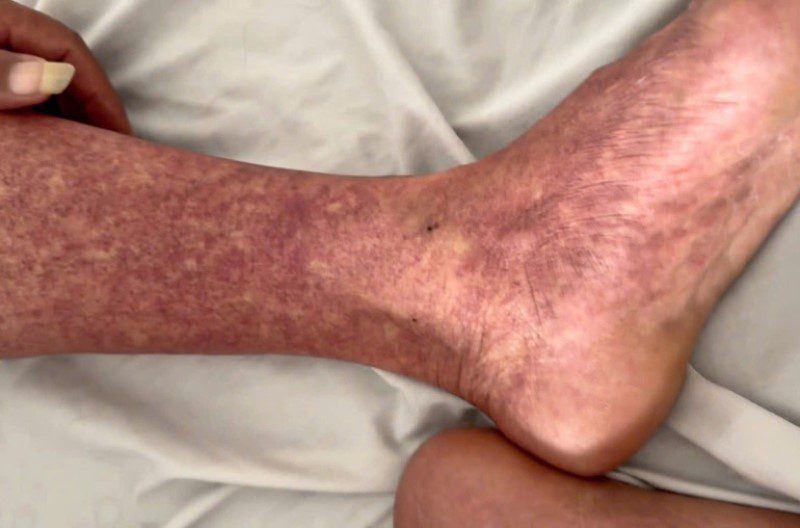

Tại Khoa Cấp cứu, bệnh nhân ở ngày thứ 5 của bệnh, da nổi vân tím vùng bụng, chân và tay, có xuất huyết rải rác vùng cẳng chân, có dấu hiệu nhiễm trùng, thở nhanh phải hỗ trợ thở ô-xy.

Bệnh nhân xuất huyết ngoài da.

Tình trạng xuất huyết ngoài da.